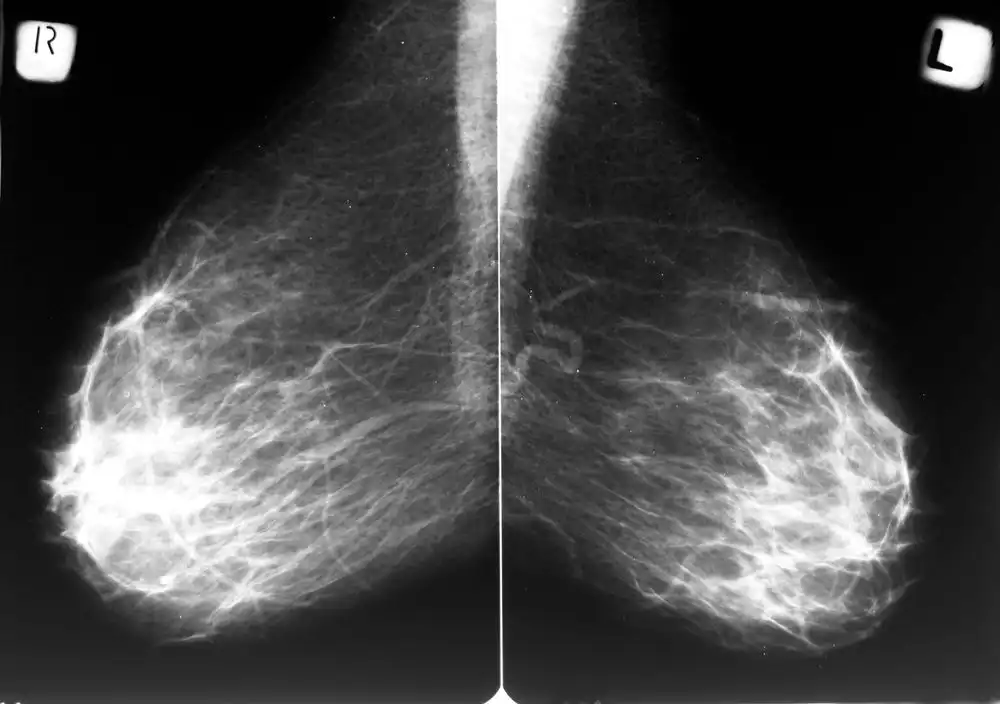

Studien beweisen: Mammografie verursacht Brustkrebs

Wie alte Studien vermuteten und neue beweisen können, besteht ein direkter Zusammenhang zwischen der Mammografie und Brustkrebs. Dass ausgerechnet die Brustkrebs-Vorsorge diesen auslösen kann, ist besonders erschreckend, weil die meisten Schulmediziner dies verneinen. Im Gegenteil: Noch immer gilt die Röntgenuntersuchung der Brustdrüsen als populärste Methode, Brustkrebs zu entdecken – den sie selbst verursacht.